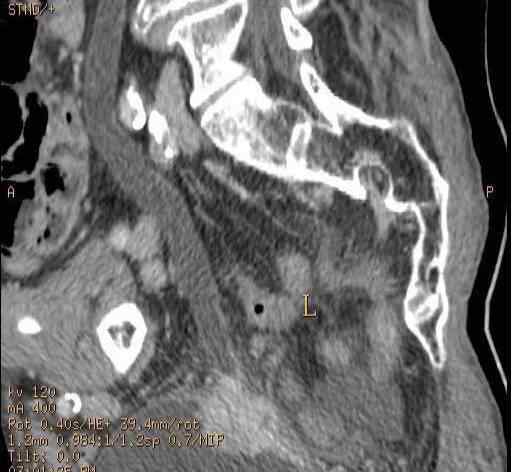

扫描后重建泌尿系统显示左侧输尿管中部有结石。

静脉注射造影剂后,经一定时间延迟后进行扫描重建,结石阴影与造影剂对比良好。